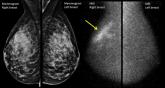

The better mammogram: Experts explore sensitivity of new modalities

PHILADELPHIA – Newer technologies such as tomosynthesis and molecular breast imaging could be especially helpful in screening women with dense...